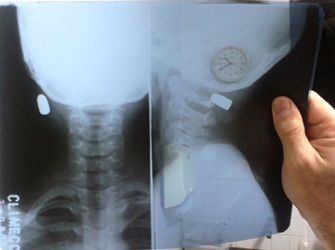

O garotinho que foi levado para a Climecc identificado por Abel Almeida do Nascimento, 12 anos, também com uma bala calibre 38 alojada na parte inferior da nuca, chamou a atenção do médico Leonardo Coelho, “ele pode comemorar duas datas de nascimento por ano, porque o que aconteceu com ele é muito raro. A bala entrou na cabeça, mas não chegou ao cérebro, pois foi segura pelo capuz da blusa que usava e o pano também entrou no couro cabeludo e não furou com a bala. Pedi imediatamente um raio-x e verifiquei que não comprometia em nada, não havia risco e resolvi retirar o projétil aqui mesmo para aliviar a tensão da família. Conceição do Coité no quesito atendimento infantil está de parabéns por ter a Climecc que atende várias cidades da região e graças a sua boa estrutura tivemos uma resposta rápida da situação do garoto e está aqui, em boas condições de saúde, não sofreu nenhuma hemorragia e está ao lado da mãe” ressaltou o plantonista.

A Polícia Militar e a Civil estiveram acompanhando a ocorrência, mas não anteciparam nada sobre o caso. Um policial civil disse que ficou surpreso com vários tiros a queima roupa, sendo que dois atingiram parte vital do corpo, no caso a cabeça das vítimas, e os projéteis não penetraram o crânio.